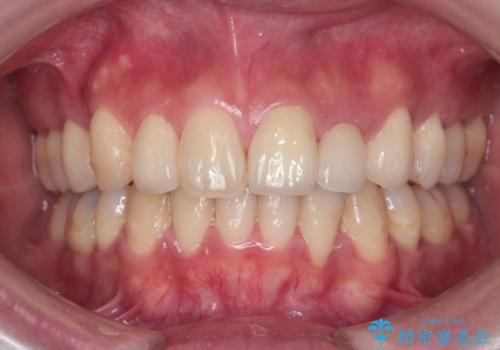

[前歯のねじれ 部分]ワイヤーとマウスピースの併用矯正治療

担当医 大元洋佑

![[前歯のねじれ 部分]ワイヤーとマウスピースの併用矯正治療 の症例 治療後](https://seimitsushinbi.jp/wp/wp-content/uploads/2024/11/d62ebcf4699c90efb9ffd5ed659b7480-500x350.jpg?v=1731313408)